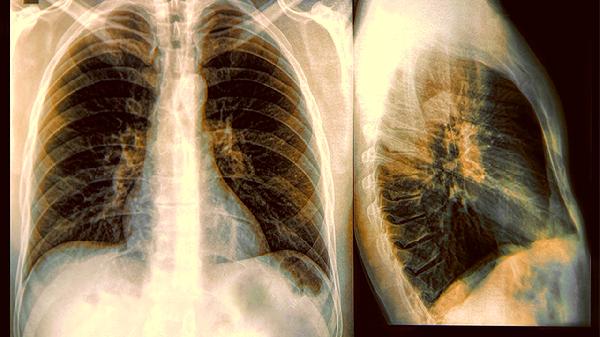

2、筛查技术的防护盾

高分辨率CT扫描能发现早期肺癌病灶,其精准度堪比军.事卫星识别地面车辆。定期检查就像给肺部安装烟雾预警器,在火势蔓延前拉响预警。